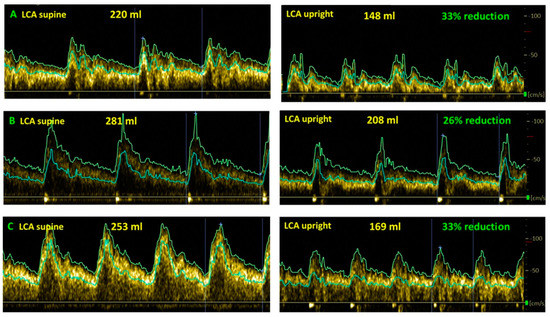

2.5. Extracranial Doppler for Cerebral Blood Flow Measurements